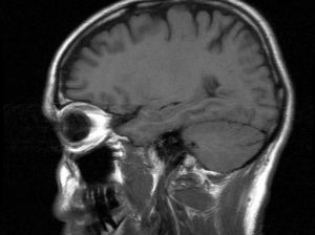

Researchers from Sweden's Uppsala University identified an important aspect of pediatric brain cancer, finding that even when cells were given the same cancer-causing genetic mutation, the tumor did not always turn out the same way.

If this research proves to be the case, then the future job of oncologists becomes even more complicated. Once genetics have been established for a cancer, the place of origin also has to be determined.